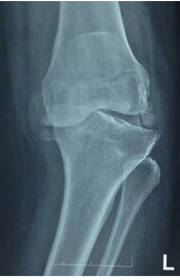

It also means resurfacing. The worn-out cartilage surface is removed and lined with smooth… View More16 Feb 2021

It means to remove the old implant and put a new one. The most common causes are Aseptic L… View More03 Dec 2020